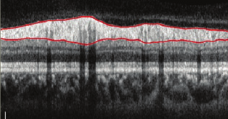

Epiretinal Membrane